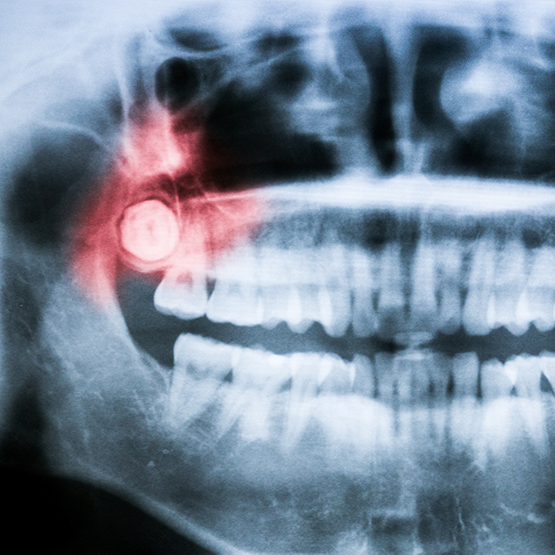

X-ray showing an impacted wisdom tooth

If your wisdom teeth have erupted through the gum line and are visible, Dr. Gaddam can likely remove them in-house. Using an instrument called an elevator, she’ll gently lift the wisdom teeth from their socket. Then, our team will remove them from the mouth with a pair of dental forceps and wiggle them free of any connective tissues. Before you leave, we’ll provide you with aftercare instructions to prevent complications like dry socket from occurring.